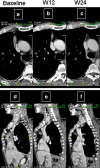

Treatment of malignant pleural mesothelioma (MPM) represents a highly unmet medical need. Here, we discuss the results and therapeutic potential of first- and second-generation immunomodulatory antibodies targeting distinct immune checkpoints for the treatment of MPM, as well as their prospective therapeutic role in combination strategies. We also discuss the role of appropriate radiological criteria of response for MPM and the potential need of ad hoc criteria of disease evaluation in MPM patients undergoing treatment with immunotherapeutic agents.